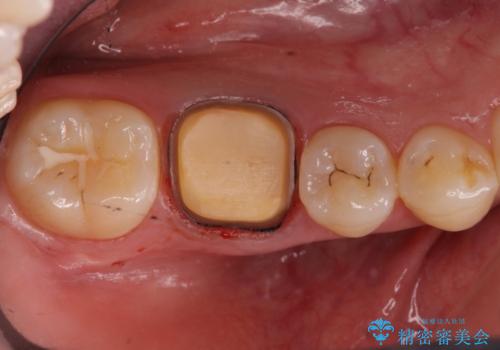

- 樹脂をやり替えたいとのことで来院されました。

特に大きな虫歯もありませんでしたが、残った歯が薄かったためクラウンでの修復処置を行いました。

インレーにすると残った歯が薄くなってしまう場合は術後の破折リスクが高いためクラウンで修復することがあります。